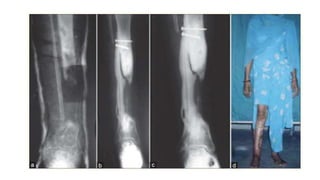

Ilizarov method

• Law of tension stress and distraction osteogenesis

• Corticotomy is done in the fracture fragments and both the fragments

are distracted.

• When the desired length is achieved, distraction is stopped and

consolidation of the new bone formed occurs

• Gold standard in infective gap non union

• Fibular osteotomy

• Removal of fixator:

Atleast three cortices should be ossified in AP and Lat view xrays

Protected weight bearing

Ilizarov method • Lawof tension stress and distraction osteogenesis • Corticotomy is done in the fracture fragments and both the fragments are distracted. • When the desired length is achieved, distraction is stopped and consolidation of the new bone formed occurs • Gold standard in infective gap non union • Fibular osteotomy

• 21.

• Removal offixator: Atleast three cortices should be ossified in AP and Lat view xrays Protected weight bearing • Advantages: no skin incision is made, minimally invasive (wires and pins) Very little soft tissue handling Can correct length and deformities in three dimensions Patient can weight bear early after application